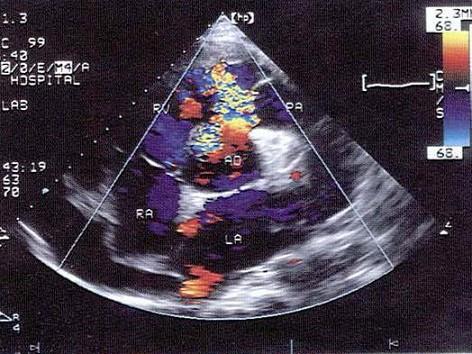

该病例最可能的诊断?(?)A.右室流出道狭窄B.室间隔缺损C.主动脉右冠窦瘤破裂D.主动脉右冠瓣脱垂E.房间隔膨出瘤

问题 该病例最可能的诊断?(?)

选项 A.右室流出道狭窄 B.室间隔缺损 C.主动脉右冠窦瘤破裂 D.主动脉右冠瓣脱垂 E.房间隔膨出瘤

答案 C